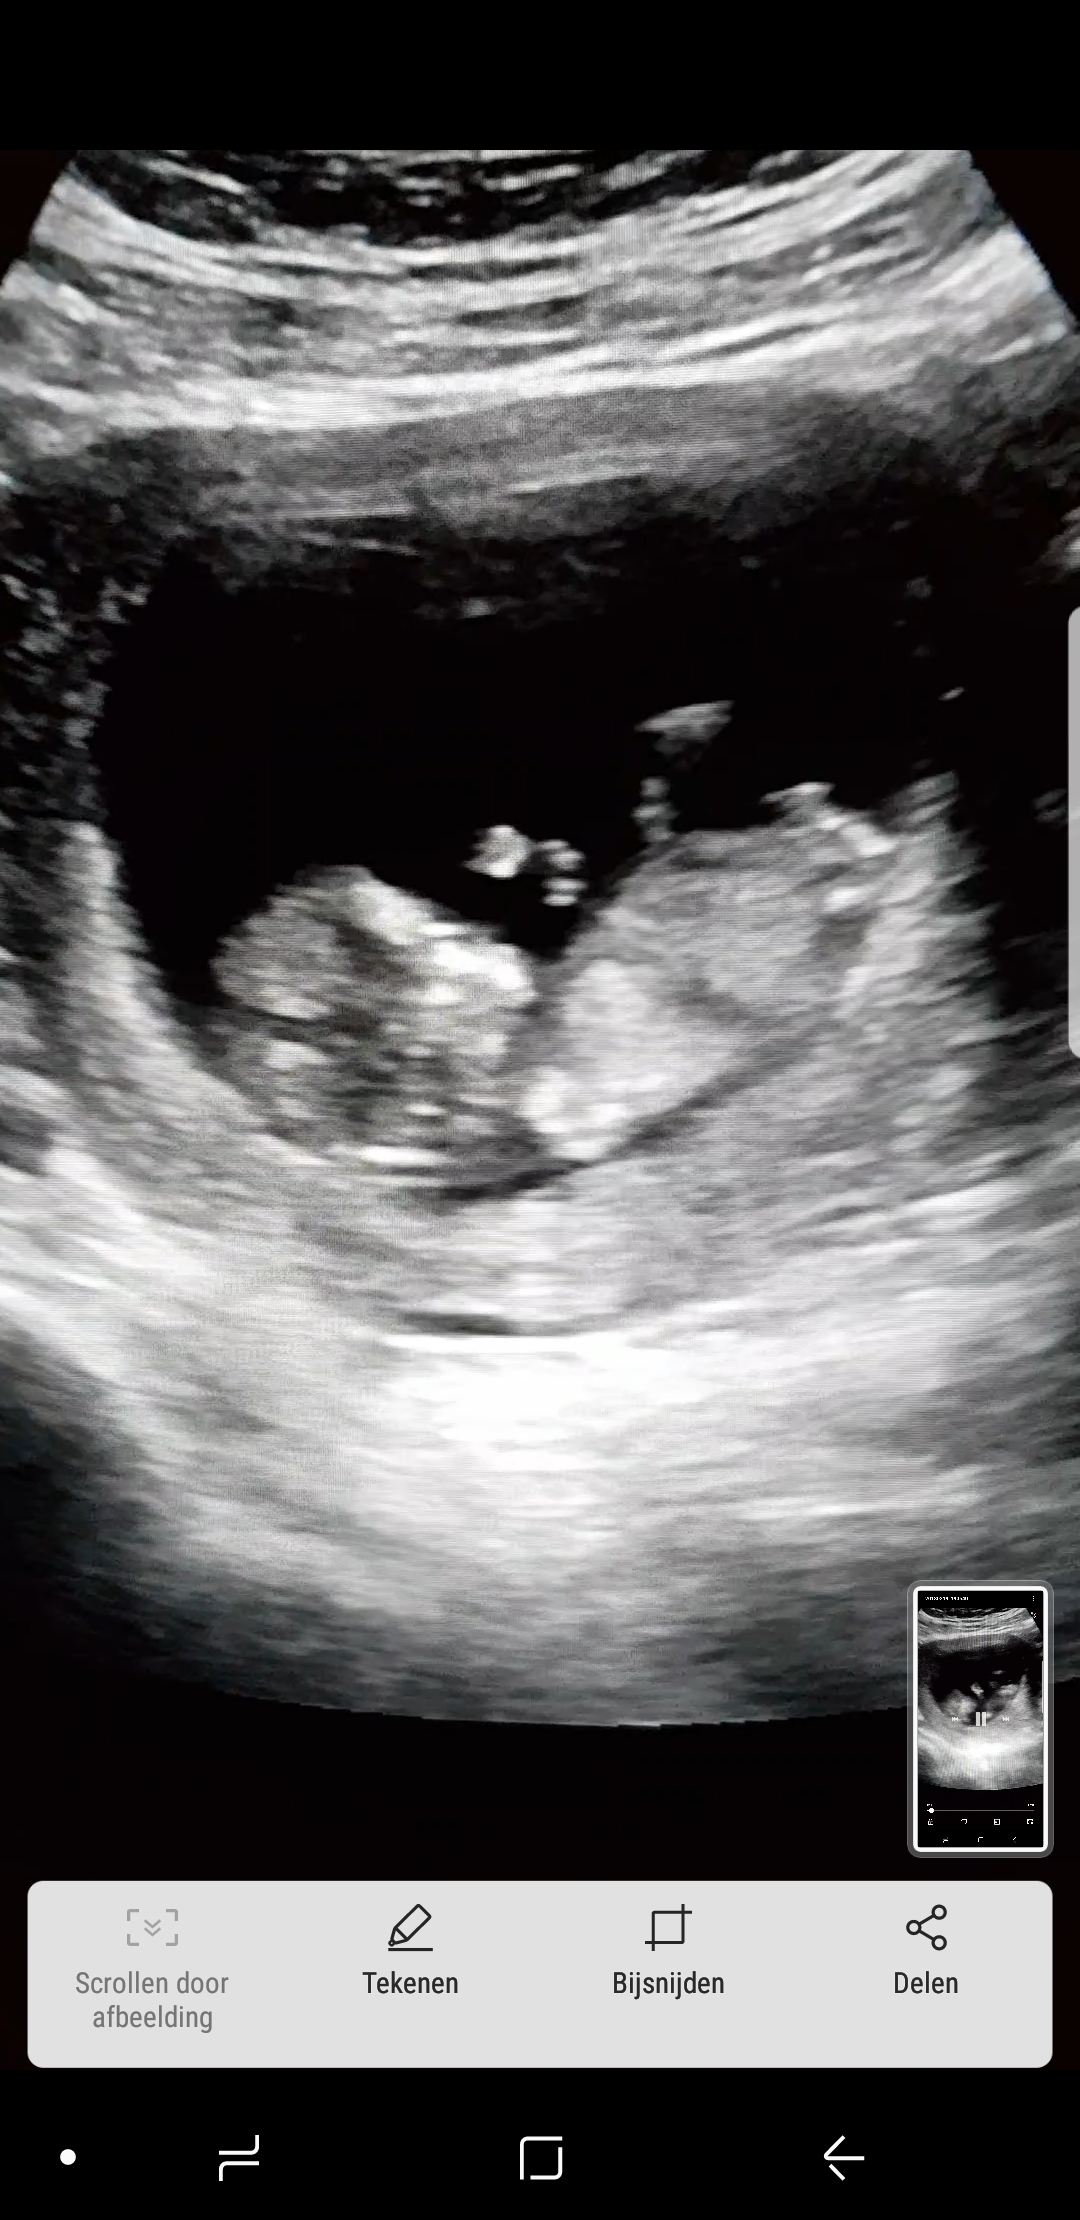

Merhaba araniza yeni katildim 12+3 haftalik hamileyim ama cinsiyeti henuz belli degil, banada yorum yapabilirmisiniz

• 1520094421057867992904.jpg